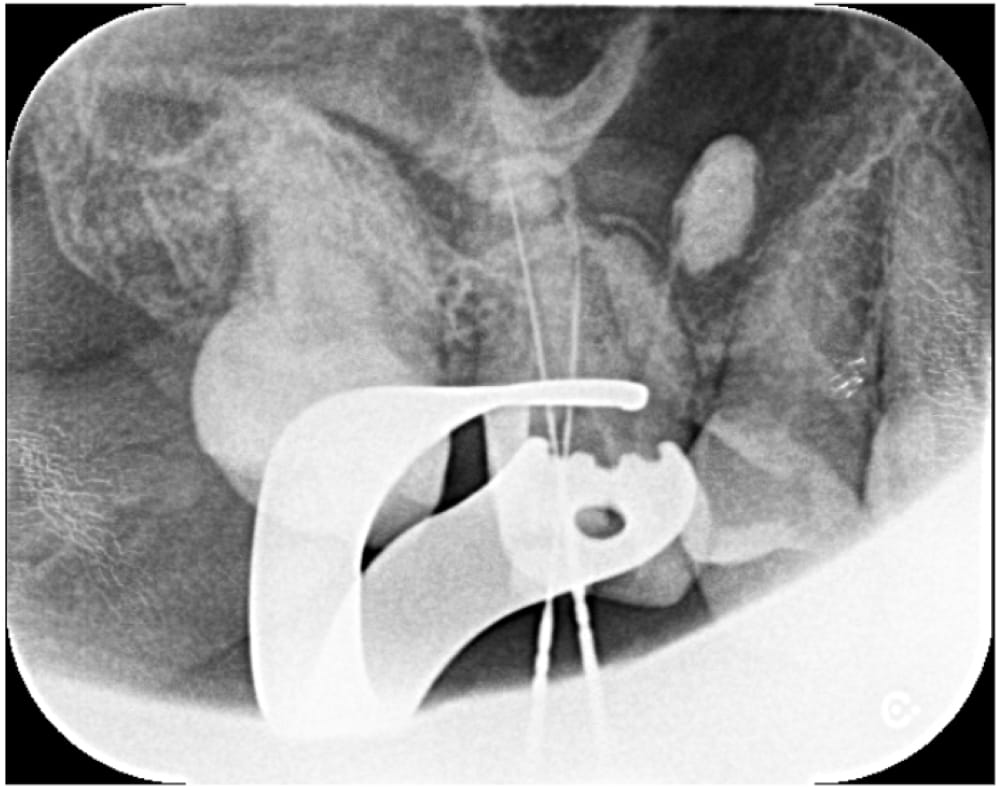

根管内の古い詰め物をすべて除去し、本来の異なる方向に穴があいているパーフォレーション部位に対しては、MTAセメントを使用して穿孔封鎖を行いました。

治療は2回で完了し、飛び出ている材料の状態も含め、経過観察となりました。